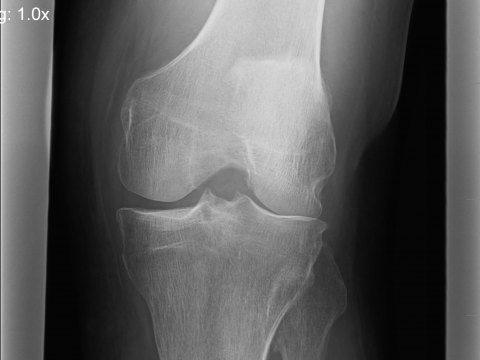

Zunächst versuchen wir das Gelenk im Detail anzuschauen. Wie stellen sich Knorpel, Meniskus, Bänder und Gelenkschleimhaut dar? In welchem Ausmaß und in welchem Bereich des Gelenkes finden sich Veränderungen? Hierzu können wir auch vorhandene Unterlagen (MRT, Röntgen) nutzen oder gegebenenfalls ergänzen. Zur aktuellen Einschätzung von Entzündung oder Reizung führen wir zusätzlich eine hochauflösende Ultraschalluntersuchung des Kniegelenkes in verschiedenen Positionen durch.